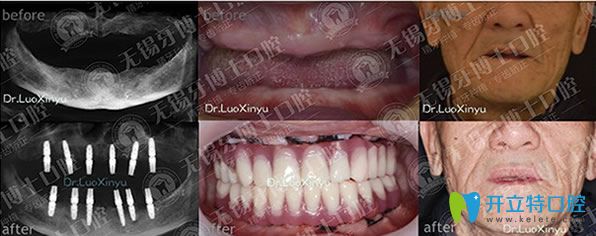

牙博士口腔種牙好不好,樸東信院長(zhǎng)全口種植牙代表案例:

牙博士口腔樸東信院長(zhǎng)全口種植牙代表案例

無(wú)錫牙博士口腔樸東信院長(zhǎng),種植牙技術(shù)適用于各種缺牙類(lèi)型,美觀(guān)舒適,媲美真牙,咀嚼功能強(qiáng),種植牙后,想要具有和天然牙一樣的功效,長(zhǎng)期使用,需要保持良好的口腔衛(wèi)生。